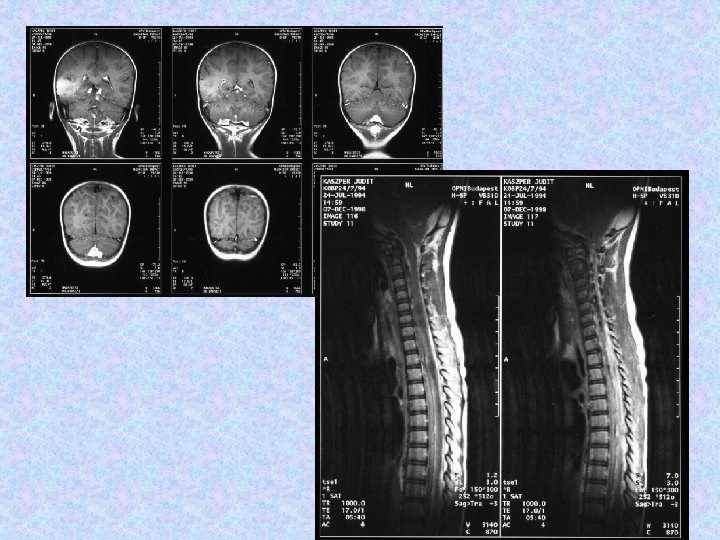

• MR vizsgálat készült liquorpassage zavar miatt. • MR vizsgálat meningeális kontraszthalmozást mutatott a bazális ciszterna, a cerebri media, a ciszterna magna területében. • Felmerült a meningitis basilaris gyanúja, amely nem igazolódott. • Liquor fehérje: 7, 05 g/l, glükóz: 5, 0 mmol/l, sejtszám 10/látótér. Baktérium nem tenyészett ki. Mikrobiológia, szerológia negatív. Citológia gyulladásos szedimentációt véleményezett. Tumor sejtek nem voltak láthatóak. • Spinalis MR thoracalis compressziót, meningeális szóródást mutatott.

• 1998. június 30 -án jobb oldali VP shunt került behelyezésre. Biopsziát későbbre terveztek. • 1998. július 20 -án készült CT beszűkült szupratentoriális kamrarendszert mutat. A shunt jó pozícióban helyezkedik el. • Az 1998. augusztusi MRI nem mutat progressziót sem a kraniális, sem a spinális folyamatokban. • Az 1998. december 7 -i MR felvétel progressziót mutat. Neurológiailag a betegnek kétoldali Babinski tünetei, élénk mélyízületi reflexei vannak, izomzata hypotoniás. Egyebekben negatív státusz. A shunt közepes nyomás mellett jól vezet.